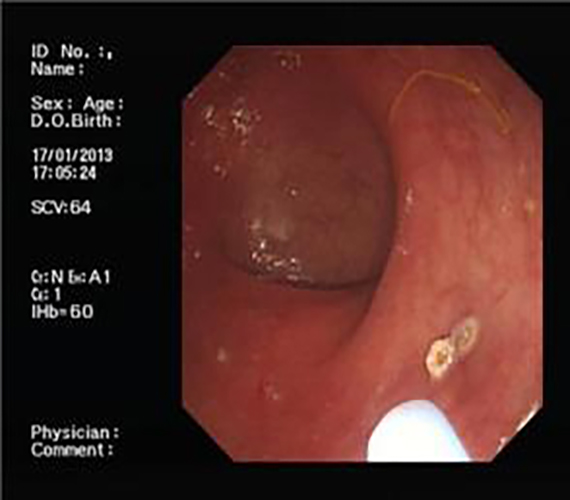

腺性胃息肉

腺瘤性胃息肉

胃息肉做手術

胃息肉治療前後